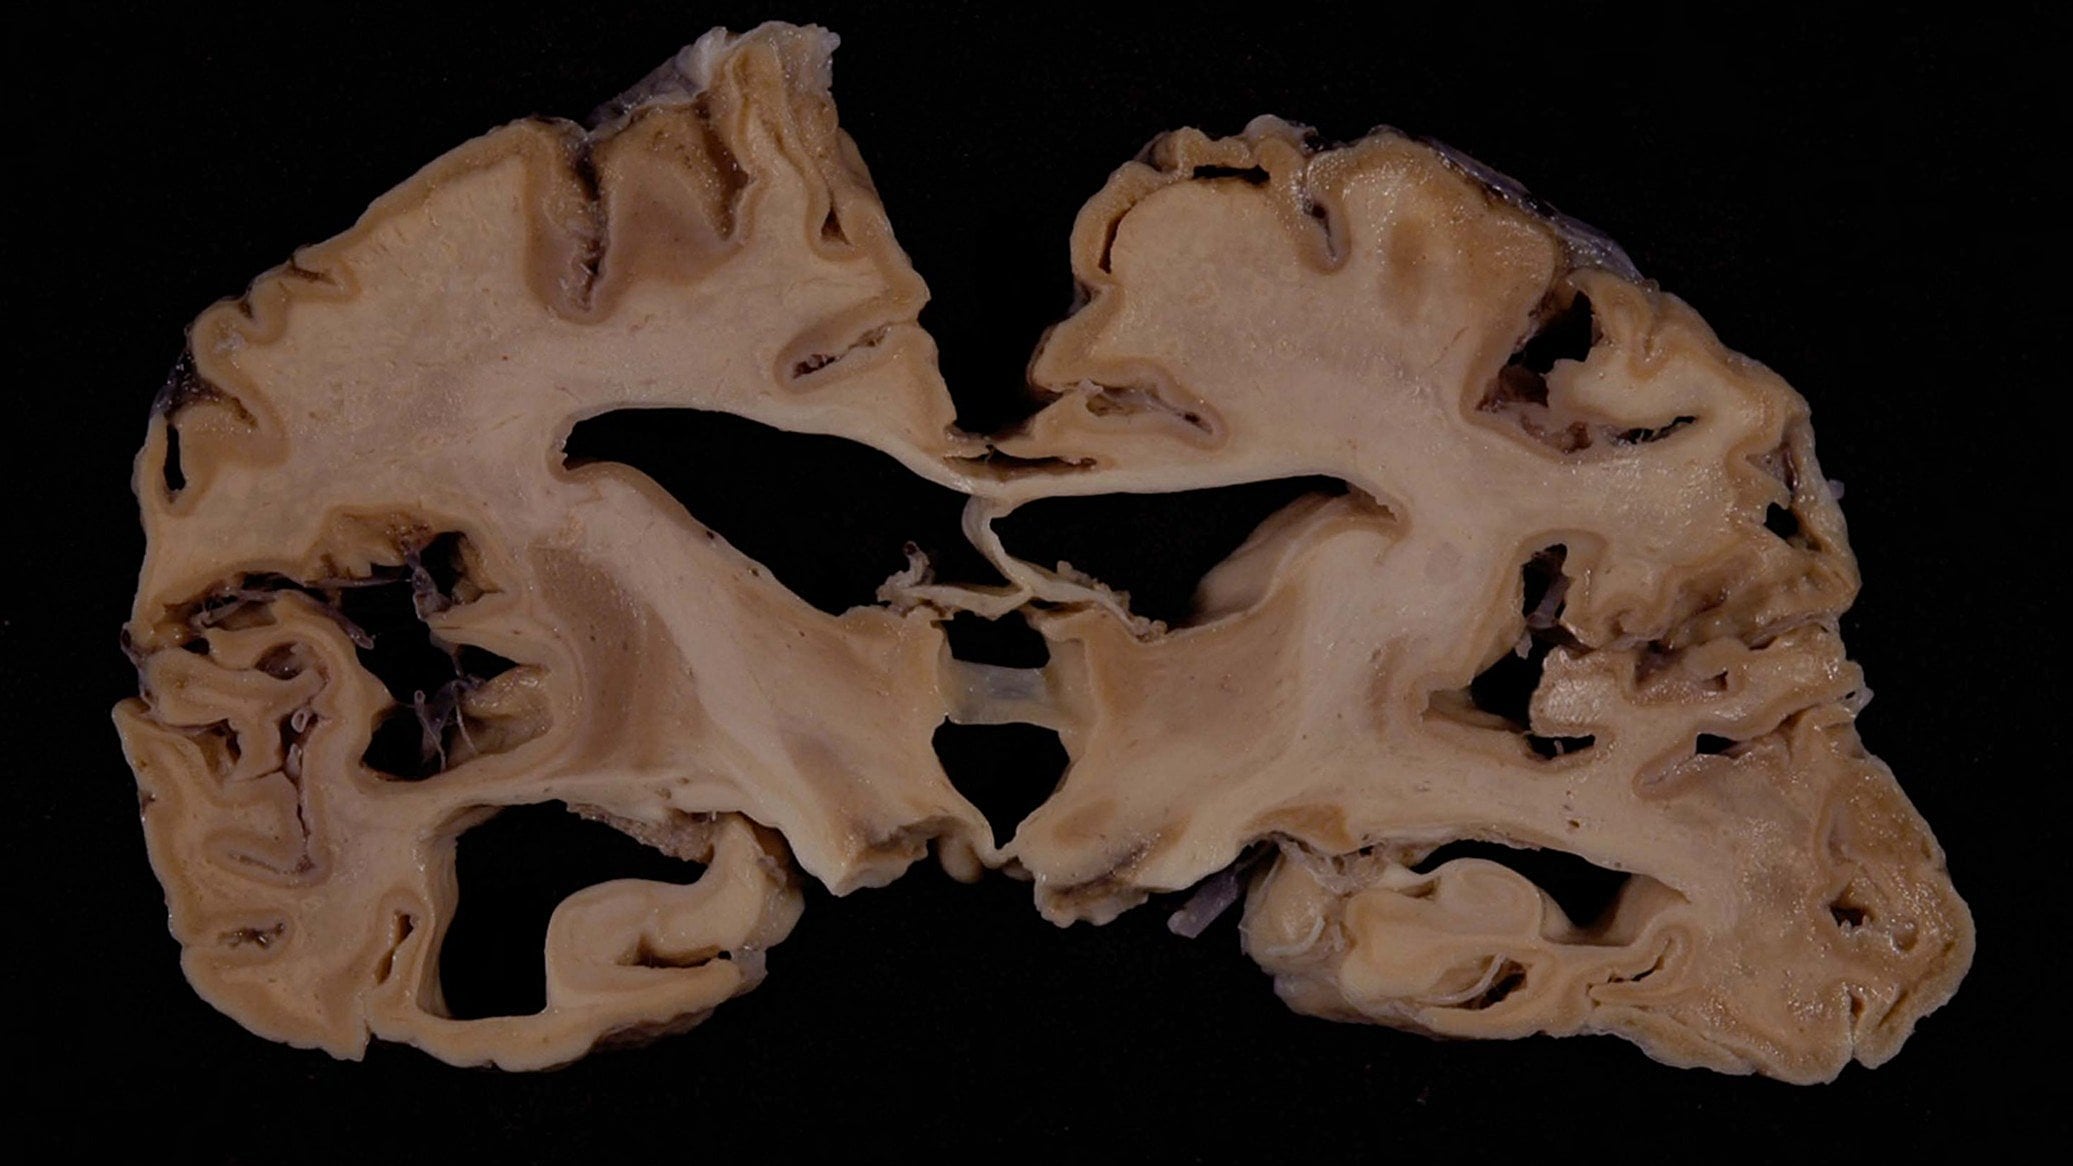

Creutzfeldt-Jacob hastalığı ve varyantları, bulaşıcı spongiform ensefalopatiler (BSE'ler) olarak bilinen geniş bir insan ve hayvan hastalıkları grubuna dahildir. Adı, etkilenen beyin dokusunda gelişen, mikroskop altında görülebilen süngerimsi deliklerden türetilmiştir. "Prion" kelimesi 1982'de protein yanlış katlanması nedeniyle önceden bilinmeyen enfeksiyon formuna atıfta bulunarak "proteinli" ve "enfeksiyon" kelimelerinden türetilmiştir. Prionlar, 1997 yılında fizyoloji veya tıp alanında Nobel Ödülü kazanmış Stanley Prusiner tarafından adlandırılmıştır ve keşfedilmiştir.

Normal hücresel prion proteini (PrP), sağlıklı insanların ve hayvanların hücre zarlarında bulunur. Henüz tam olarak keşfedilmemiş karmaşık işlevlere sahiptir. Creutzfeldt-Jacob hastalığı normal hücresel prion proteini Prp'nin anormal, yapısal olarak değişmiş, hastalığa sebep olan prion PRP scarpie adı verilen bir forma dönüşmesinden kaynaklanır ve bu durum ilerleyerek beyin boyunca birikir. Anormal protein, scarpie ismini koyun ve keçilerde rastlanan prion hastalığı tipinden alır. PrP scarpie olarak bilinen bu enfeksiyöz izoform, doğal prion proteinlerinde yapısal bir değişikliği indükleyerek normal PrP proteinlerini enfeksiyöz izoforma dönüşmesi için tetikler. Bu durum prion hastalıklarının enfeksiyon kapasitesini açıklar. Hem normal prion proteinlerinin anormal izoforma dönüşmesi hem de anormal prion birikiminin nörodejenerasyona yol açtığına inanılmaktadır.

Hastalık ilerleyicidir ve genelde tüm beyin dokusunu tutarak panensefalopati tablosuna erişebilir. 1981'den beri hastaların 2.5 yıldan daha fazla yaşamadığı kaydedilmiştir.